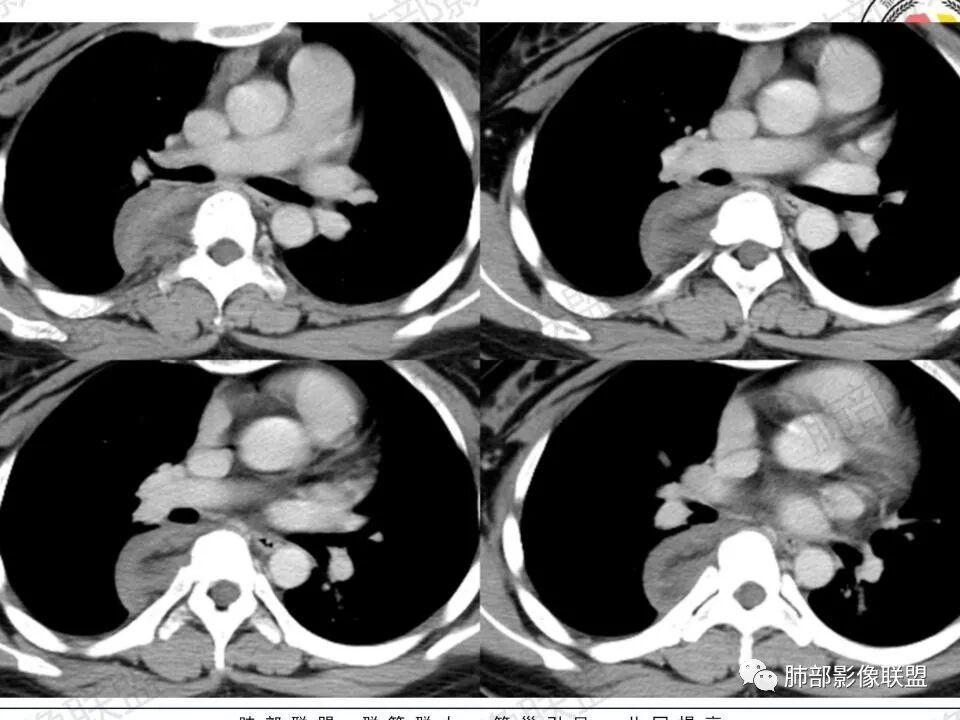

3.块影血供动脉来自肋间动脉,且由内后方侧入,其与下腔静脉之间未见回流通道。血管未见破坏,相邻组织未见侵入。

瘤体体积常较大,大部分有完整包膜,边界清楚,可沿周围组织间隙嵌入性生长,由于肿瘤质地较软,使得肿瘤可呈多种形态,其易沿着周围组织间隙生长、包饶,但不挤压周围器官或组织,邻近血管被包绕或穿行,呈嵌入式或铸型生长方式,这是后纵隔神经节细胞瘤的特征性表现;

还有另外一种形态学特征,瘤体的上下径线常大于其他径线,这可能是神经节细胞瘤起源于交感神经节,而交感神经节纵向分布于近脊柱中线两旁及前方,导致了后纵隔神经节细胞瘤纵向生长的范围大于向其他方向生长的范围,其上下可跨越多个椎体。但后纵隔神经节细胞瘤体积较小时,则常呈圆形、椭圆形、哑铃形等形态,紧贴后纵隔或后胸壁。

CT上大部分的后纵隔神经节细胞瘤呈较均匀性低密度或稍低密度影,低于肌肉密度,这主要是由于瘤体的密度根据其内含有不同比例的黏液基质与节细胞纤维成份而不同,cT值一般约20~40 HU 但其多数密度均匀,部分甚至可接近囊性低密度,这与组织学上神经节细胞胞浆丰富,瘤内含有大量黏液基质相关。MRI 上后纵隔神经节细胞瘤多呈 T1wl 低信号T2wl稍高/高信号,其中夹杂的低信号多为胶原纤维或施万细胞成分,这些低信号可纵横交错分布呈曲线或线状,这可认为是神经节细胞瘤的特征性MR表现,本组3例可见该征象。有学者报道,部分神经节细胞瘤可出现脂肪密度信号影,后纵隔肿瘤内出现脂肪密度/信号是诊断神经节细胞瘤的一种较特异性表现。神经节细胞瘤的钙化率20%~42%,钙化多呈斑点状,很少出现不规则或不均质的形态,散在点状或沙粒状是神经节细胞瘤的特征,而粗大条状或不定形则倾向恶性。

后纵隔神经节细胞瘤常动脉期无明显強化、或轻度间隔、包膜或瘤体强化,延迟期可进一步斑片、结节状轻度或中度强化,强化程度进行增加,呈渐进性延迟强化,但強化程度一般为轻度到中度强化,究其原因可能是神经节细胞瘤瘤体内含有大量黏液基质和胶原纤维,使得细胞外间隙扩大,阻碍了对比剂的灌注,从而延缓了对比剂的积累,因此其动脉期多无明显强化或仅有轻度强化,延迟期呈渐进性轻度强化是后纵隔神经节细胞瘤强化特征。大部分病灶有轻度-中度强化,部分病灶无强化,这还可能与瘤组织内部间质血管含量多少相关,无强化病例瘤组织内部主要由胶质纤维和节细胞组成,间质血管较少,因此强化较低,而强化程度较高的病理可见较多的扩张、充血的毛细血管,引起较多的对比剂积蓄,因此强化相对明显。因此,神经节细胞瘤极少出现瘤组织早期强化,而多呈延长渐进性强化,增强扫描神经节细胞瘤内细胞成分可增强,黏液基质不强化。

总结:后纵隔神经节细胞瘤的影像学表现有一定特征性:其好发于儿童或青少年,女性多见,肿瘤常位于后上纵隔,瘤体较大,上下径大于其他径线,常呈嵌入式生长方式,包饶或推挤邻近器官、血管,边界清楚。CT 平扫肿瘤多数呈均匀低密度,低于肌肉密度,瘤内钙化大多为散在斑点状钙化,偶尔出现脂肪密度是特征性表现。MR平扫呈长T1长T2信号, 有时可见瘤内低信号(胶原纤维)。增强扫描早期无明显强化或轻度强化,延迟渐进陛轻度强化是其特征。